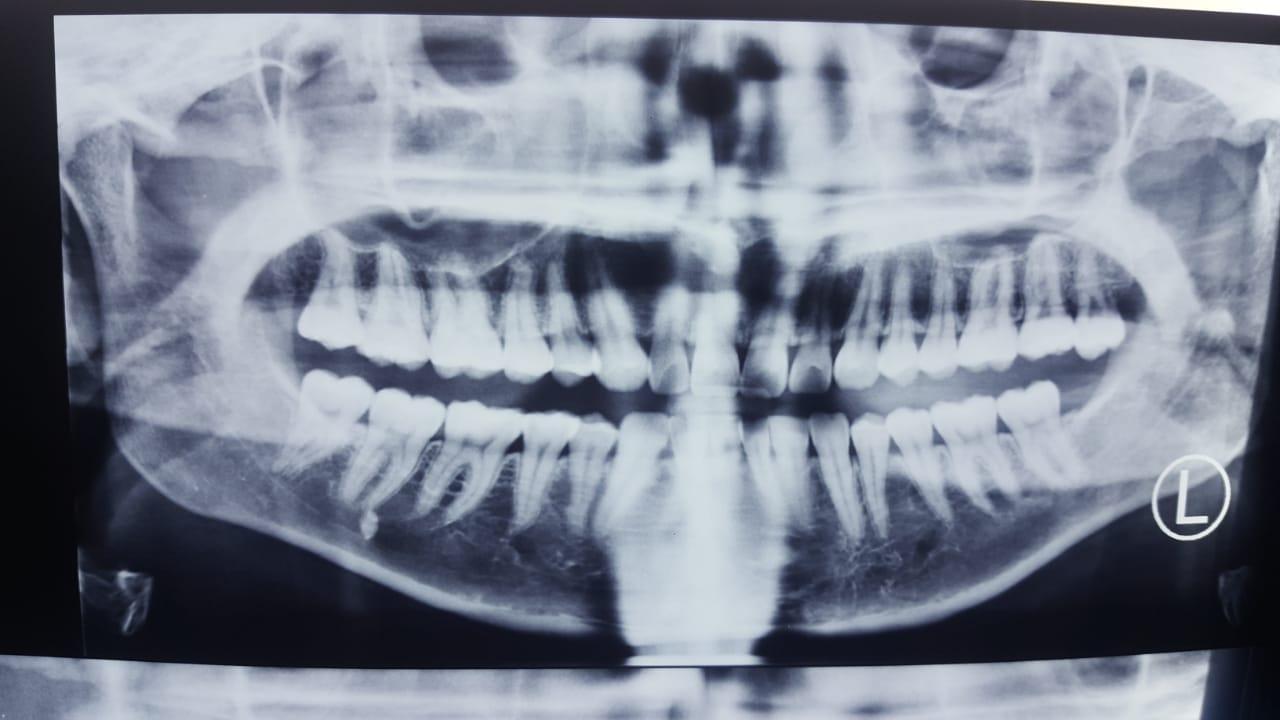

Рентгеновские снимки посттравматического остеомиелита челюсти: Медицинские случаи

Раздел: Образы вокруг